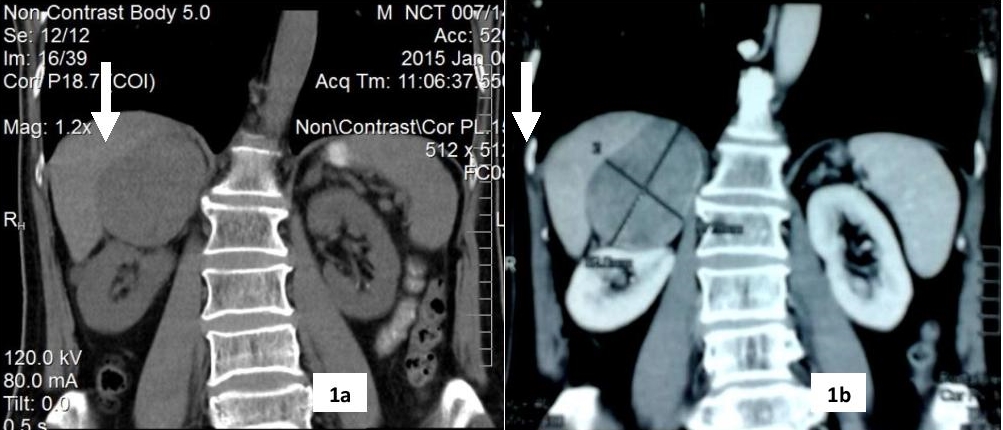

The patient had hypertension for 10 years, well controlled with amlodipine 5 mg once a day. Physical examination was unremarkable, apart from bilateral gynaecomastia with areolar tissue 2 x 3 cm in both breasts. Chest and abdominal examination were unremarkable. Blood for complete picture, renal function, serum electrolytes were all within normal limits. Ultrasound of the abdomen revealed a well defined, hyperechoic mass in the upper pole of the right kidney (adrenal tumour) measuring 6.2 x 5.1 x 5 cm. The liver and hepatobiliary tree appeared normal. Ultrasound of the testes showed bilateral atrophic testes. The right adrenal mass was subsequently confirmed by contrast enhanced computerized tomography (CECT) of the abdomen, which showed an oval shaped lesion measuring 7.8 x 6.6 x 7.4 cm (Figure 1a-b). The left adrenal gland also had a 1.3 cm nodule. Because of his gynaecomastia and hypogonadism, testosterone, estradiol, human chorionic gonadotrophin (β-hCG), lutenizing hormone and prolactin were done to evaluate the cause. (Table 1). Adrenocortical hormones were measured by doing an 8 am cortisol, urinary metanephrine and normetanephrine all of which were normal. He subsequently underwent right adrenalectomy by laparotomy.

Figure 1a-b. Abdominal scan showing right adrenal mass. 1a. Without contrast. 1b. With contrast enhancement.